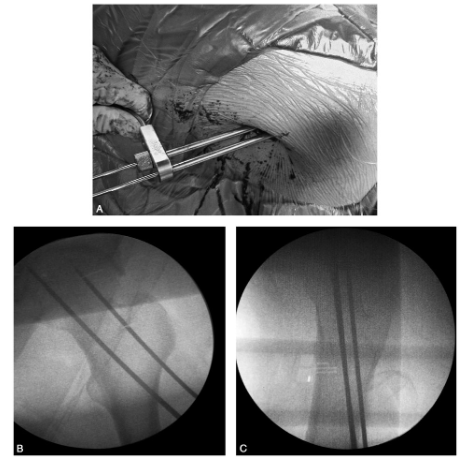

图62-4 平行导向器的使用及空心钉导针置放A.平行导向器的使用;B、C.正侧位影像中的导针位置,呈正三角形平行分布,导针位置应尽量分散

闭合复位满意者,可在大转子下3~4cm处作约2cm皮肤切口,切开阔筋膜。影像监视下首先打入近侧(或远侧)1枚导针,再通过平行导向器打入另两枚导针。通常3枚导针呈正三角形分布,3枚导针应尽量分散,避免集中。下方两枚导针尽量贴近股骨颈内侧皮质,以增加螺钉在骨内的把持力,但其入点不能低于小转子下缘,以免术后发生转子下骨折。

上方导针在侧位影像上位于股骨颈中部或偏前侧,以避开股骨颈后上方滋养动脉进入股骨头的主要区域(图62-4)。通常用3枚7.3mm自攻空心螺钉固定,钻孔时钻透皮质即可,不需攻丝,最好选用钛材料螺钉,以方便术后MRI检查。对于股骨颈后方皮质粉碎或有缺损者,应首先拧紧前方2枚螺钉,最后拧紧后方螺钉时避免加压,以免股骨颈后方压缩,骨折端向前成角。同样对于上方皮质有压缩者(外展嵌插型骨折),应最后拧紧上方螺钉,并避免加压。对于骨质较差者,螺钉尾部必须加用垫片。螺钉尖部距股骨头软骨面下应在5~10mm;为避免螺钉尖端穿出股骨头,通过多角度透视加以确认。